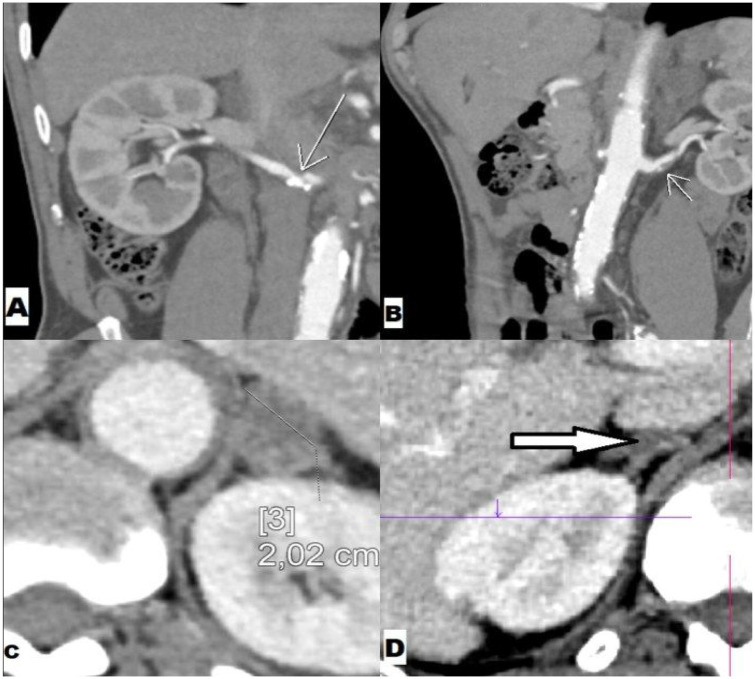

We report a case of a very rare association of adrenal adenoma, unilateral adrenal hyperplasia, and bilateral renal artery stenosis. A 61-year-old man with a remarkable history of two severe strokes was admitted to the Nephrology department with hypertension associated with severe hypokalemia and metabolic alkalosis. Doppler of renal arteries was not conclusive, so contrast-enhanced scanning was done revealing a left adrenal adenoma, right adrenal hyperplasia, and bilateral moderate renal artery stenosis. After control of blood pressure with central anti-hypertensive drugs and calcium channel blockers and normalization of kalemia under potassium supplementation, the hormonal analysis was done showing an elevated plasma aldosterone concentration at 1,568 pmol/L, with a direct renin concentration below the detection level. Primary aldosteronism was confirmed and the prescription of an anti-aldosterone agent led to the control of blood pressure and potassium plasmatic levels. In front of arterial hypertension with hypokalemia, we recommend the assessment of secondary and primary hyperaldosteronism in a systematic way since the association of two or even three etiologies of hyperaldosteronism is possible and an appropriate diagnosis is essential for adequate treatment.